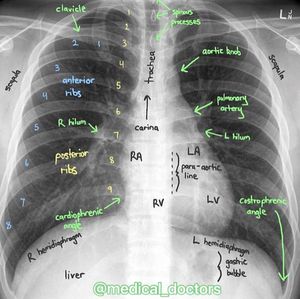

Reading a x ray

Chest X-Rays